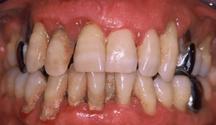

Figure 6.2.a : Parodontite chez un patient de 45 ans. De nombreux dépôts de tartre et de plaque dentaire sont visibles à la surface des dents. La gencive présente une certaine inflammation.